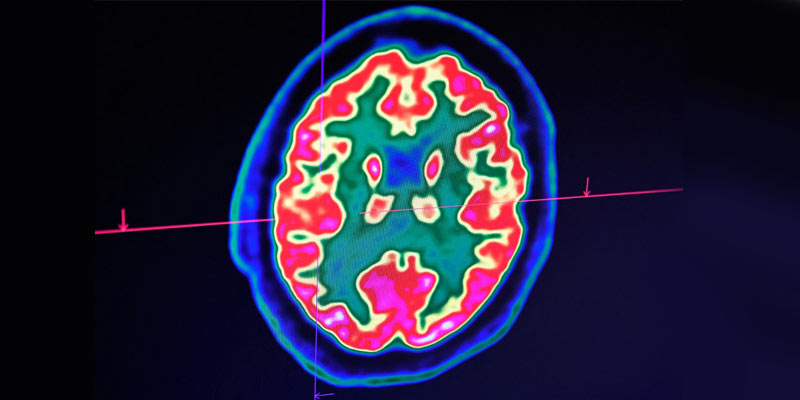

Study discovers new brain cells that help to remember objects

• Researchers have discovered a new type of brain cell that plays a central role in our ability to remember and recognise objects.

• Called ‘ovoid cells’, these highly-specialised neurons activate each time we encounter something new, triggering a process that stores those objects in memory and allowing us to recognise them later.

• These cells, found in the hippocampus of humans, mice, and other mammals, are essential for the formation and retention of long-term memories.